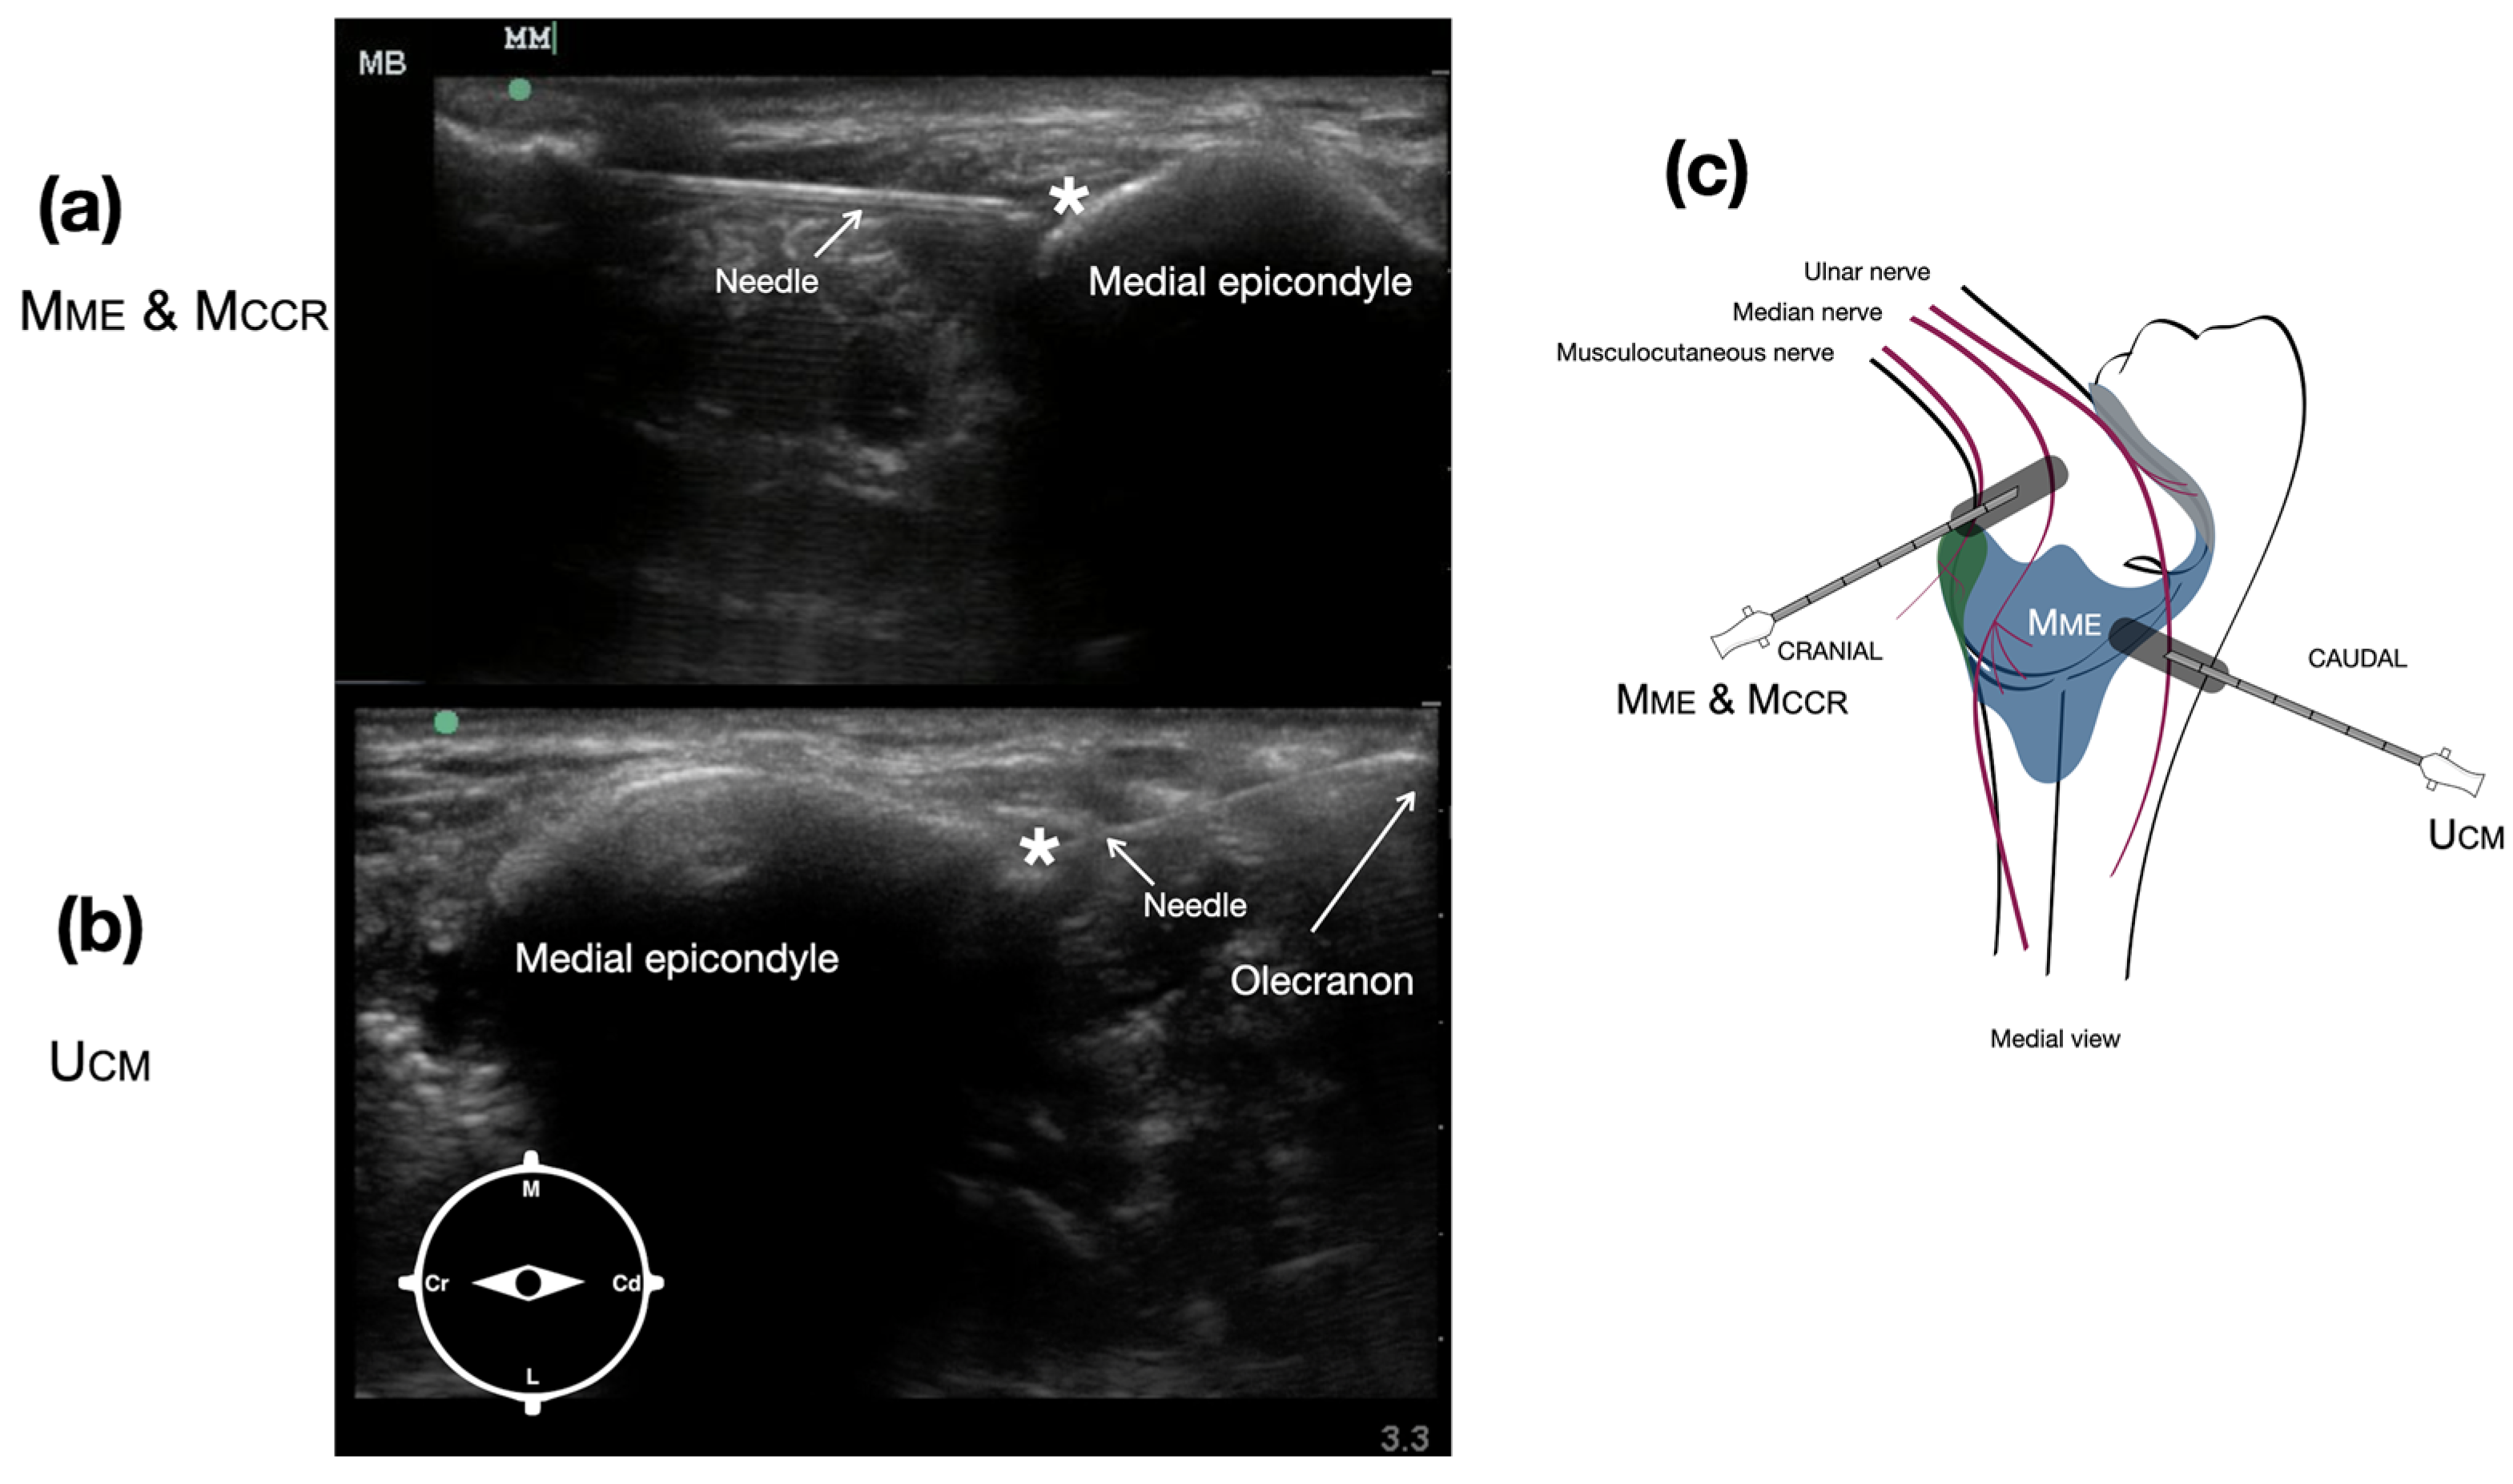

The injection site targeting the articular branches of the median nerve (Mme) and the musculocutaneous nerve (Mccr), which supply the medial and cranial quadrants of the joint capsule, respectively, was identified as a common injection point. The transducer was positioned on the medial aspect of the brachial region, perpendicular to the long axis of the distal humerus, to visualize the belly of the biceps brachii muscle. The transducer was slid distally following the insertion tendon of the biceps until the medial epicondyle was visualized (Figure 3a). The needle was then introduced in a cranial-to-caudal direction, lateral to the belly of the biceps, and advanced until it contacted the craniolateral aspect of the medial epicondyle, where the dye was injected (Figure 3a).

To access the articular branches of the ulnar nerve (Ucm), which supply the caudomedial quadrant of the joint capsule, the transducer was placed on the caudomedial aspect of the elbow using the medial epicondyle and the olecranon as ultrasonographic landmarks (Figure 3b). The needle was introduced in a caudal-to-cranial direction and guided to the caudomedial aspect of the medial epicondyle, where the dye was deposited (Figure 3b).

Figure 3. Ultrasound image of the pericapsular region of the elbow to target the articular branches of the median nerve (Mme) and the musculocutaneous nerve (Mccr) (a), which supply the medial and cranial quadrants of the joint capsule and ulnar nerve (Ucm) (b), supplying the caudomedial quadrant of the joint capsule. Schematic representation of the transducer placement and needle direction to target the articular branches of the musculocutaneous, median, and ulnar nerves (c). * indicates the ultrasound target injection point. M: medial, L: lateral, Cr: cranial, Cd: caudal.